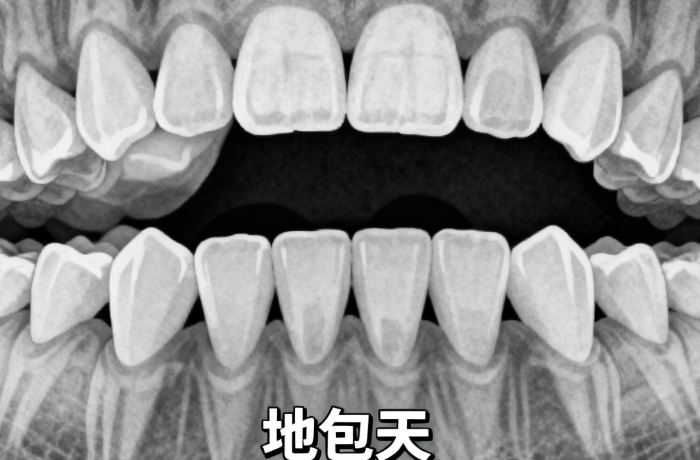

東莞口腔醫(yī)院正畸科全方面引入3D口掃、AI智能方案設(shè)計(jì)、數(shù)字化模擬預(yù)測(cè)系統(tǒng),可在治療前穩(wěn)準(zhǔn)預(yù)演矯正全過程及較終療效。無論是骨性齙牙、地包天、深覆合還是牙列擁擠,都能制定個(gè)性化方案,確?!耙淮纬C正,終身受益”。